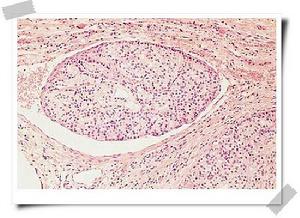

本症可由多種原因所引起。較常見者為手術後甲狀旁腺功能減退症與特發性甲狀旁腺功能減退症兩種。前者主要是由於甲狀腺手術誤將甲狀旁腺卻切除或損傷所致,但也可因甲狀旁腺手術而引起。偶或可因頸部放射治療,或其他原因進行頸部手術而損傷甲狀旁腺所致。特發性甲狀旁腺功能減退症的病因尚未明確。可能與自身免疫有關。本病患者血中可檢出甲狀旁腺抗體,同時也可有腎上腺皮質、甲狀腺或胃壁細胞抗體。還可伴有其他自身免疫性疾病如原發性甲狀腺功能減退、惡性貧血、特發性腎上腺皮質萎縮所致的Addison病等,本病可有家族史。